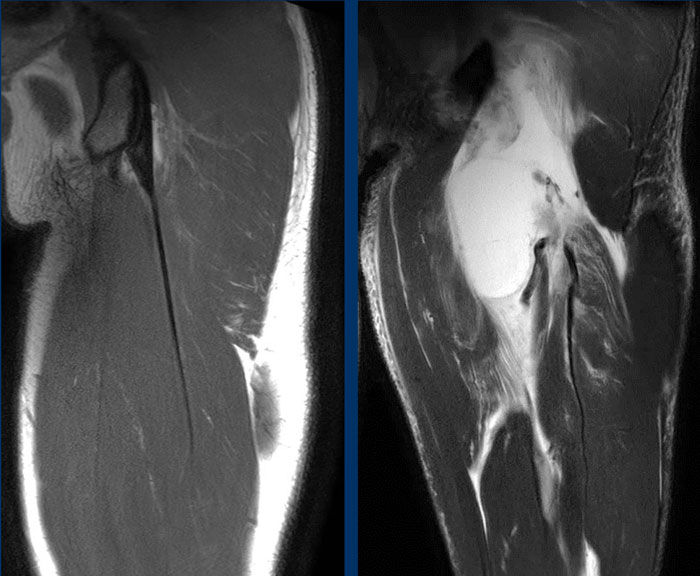

Nel caso qui sopra la lesione (fig RM a destra) riguarda invece la componente libera prossimale del tendine congiunto, avulso dalla sua inserzione ossea. La lesione è classificabile come 4 grado. A sinistra l'immagine RM del tendine normale.

La classificazione BAMIC assegna voti in base all'entità anatomica della lesione sulle immagini della risonanza magnetica (Figura sottostante). Le lesioni di grado 0 non presentano anomalie della risonanza magnetica (ma reperti clinici di lesioni muscolari) o edema muscolare a chiazze. Per le lesioni di grado 1-3, la quantità di edema muscolare (sia come percentuale dell'area della sezione trasversale nelle immagini assiali che come lunghezza cranico-caudale nelle immagini dell'asse lungo) viene utilizzata per assegnare un grado. Inoltre, la lunghezza delle fibre interrotte (se presenti) e la presenza o l'assenza di tensione persa nell'unità miotendinea prossimale o distale alla lesione è un fattore aggiuntivo. Le lesioni di grado 4 mostrano una completa rottura dell'unità miotendinea.